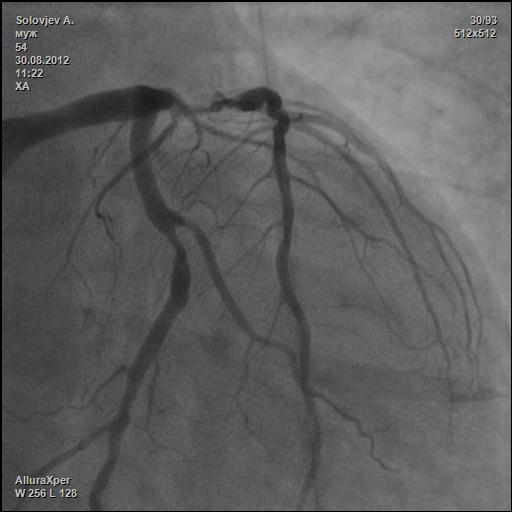

М. 54г. Ел пил все подряд. Лечили подагру, когда прижмет. Курил сигаретки. И вот тебе сюрприз.

Ваш диагноз? Как лечить?

субокклюзия передней

Расценена как окклюзия (желтая стрелка). А другие?

В проекции «Spider» - ЛКА и окклюзия ПНА смотрится понятнее (для меня естессно).

А белая стрелка показывает окклюзию диагональной ветки?

Больному было выполнено 2 АКШ и 1 МКШ.